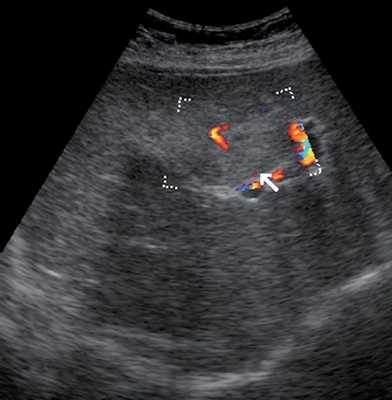

УЗИ брюшной полости. Печень увеличена в размерах, контуры ровные, структура неоднородная, средней эхогенности, признаков портальной и билиарной гипертензии нет. В правой доле печени визуализируется образование размером 142x95 мм, гиперэхогенное, выраженно неоднородное по эхоструктуре, с неровными контурами, наличием мелких эхонегативных зон, имеющее ободок пониженной эхогенности по периферии, с кальцинатами внутри. Образование гиповаскулярное. Желчный пузырь спавшийся. Поджелудочная железа без особенностей. Селезенка нормального размера, структурно не изменена.

Заключение: объемное образование правой доли печени (рис. 1).

в) Режим ЦДК. Образование гиповаскулярное. Стрелкой обозначены кальцинаты.

Типичными эхографическими признаками капиллярной гемангиомы (рис. 4) являются: небольшой размер (от 20 до 40 мм) образования, однородные, гомогенные гиперэхогенные, с четкими ровными (иногда неровными волнистыми, бугристыми в виде "штрихов") контурами, имеющие вид "спущенного шара"; хорошо отграничены от окружающей ткани; без затухания, иногда с усилением эхосигнала позади образования [1, 5, 12-14]. Типичные эхографические признаки кавернозной гемангиомы: образования больших размеров, с четкими бугристыми контурами; хорошей очерченностью от окружающей их неизмененной ткани печени; характеризуются высокой эхогенностью и неоднородностью структуры, которая обусловлена наличием кавернозных полостей, определяемых при УЗИ в виде эхонегативных зон различных форм и размеров [5, 9, 12]. При цветовом допплеровском картировании (ЦДК) кровоток в самой гемангиоме в 86,9% случаев, как правило, не определяется (образование аваскулярное или гиповаскулярное); в 75% случаев хорошо виден подходящий к гемангиоме питающий сосуд с признаками артериального, ламинарного кровотока. При оценке количественных показателей кровотока в артериях средняя систолическая линейная скорость кровотока, по данным разных исследователей, в гемангиомах составляет от 37,56±17,68 до 15,0±16,0 см/с; линейная скорость венозного кровотока в среднем достигает 20,61±9,8 см/с; PI в гемангиоме в среднем равен 0,91±0,14, RI - 0,5 [1, 5, 13-17]. Индекс допплеровской перфузии при гемангиомах - 0,22, что значительно меньше, чем при злокачественных образованиях (0,62±0,1) [1].

б) Режим ЦДК. Образование аваскулярное, вокруг образования визуализируются огибающие сосуды (стрелка).